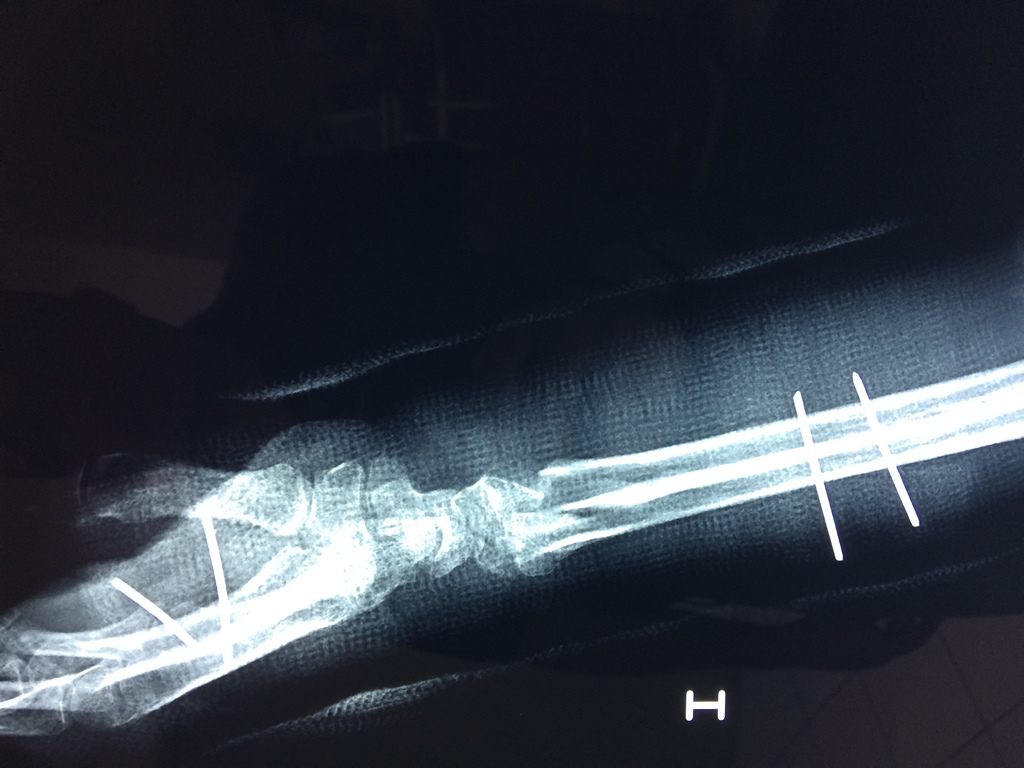

Cirugías de Codos - Cirugías de Muñecas y Manos

Los procedimientos más comunes en cirugía de la mano son aquellos destinados a reparar traumatismos, incluyendo lesiones de tendones, nervios, vasos sanguíneos, y articulaciones; huesos fracturados; y quemaduras, cortes, y otros daños de la piel.